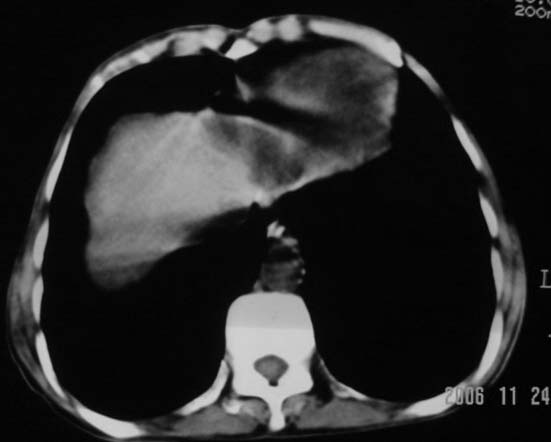

仰卧位见:肝前间隙及肝脾间隙内可见新月形气体密度影,边缘清楚,侧卧位见气体随体位改变而移动,ct值约-929hu。膈下、肝下间隙及部分肠间隙可见液性密度影。考虑:1、上腹部空腔脏器穿孔,以胃穿孔可能性大。2、少量腹水。

仰卧位见:肝前间隙及肝脾间隙内可见新月形气体密度影,边缘清楚,侧卧位见气体随体位改变而移动,ct值约-929hu。膈下、肝下间隙及部分肠间隙可见液性密度影。考虑:1、上腹部空腔脏器穿孔,结合临床,首先考虑胃穿孔可能性大。2、少量腹水

补充--肝门及肝肾间隙以见积气显示。

支持消化道空腔脏器穿孔(腹腔内大量游离气体影,小网膜囊内亦见气体影),少量腹水。